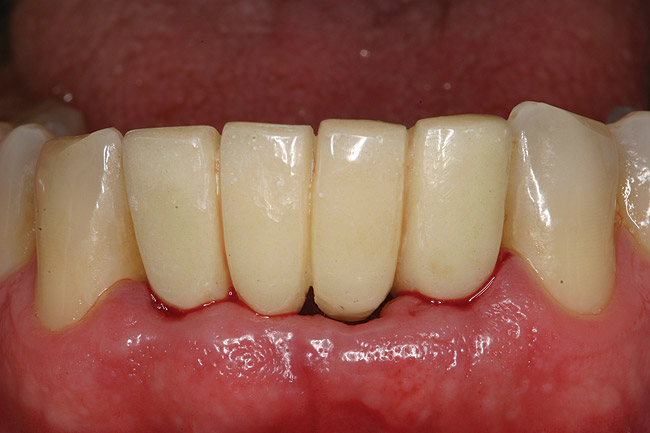

A 53-year-old male presented with localized advanced periodontal disease of the mandibular incisors. Teeth Nos. 23 to 26 exhibited Class II mobility because of advanced bone loss (Figure 1). The teeth had migrated out of position over the years, and a diastema had developed between No. 24 and No. 25 (Figure 2). The patient complained about the poor esthetic appearance of these teeth, and he was able to perceive their loss of strength on function as a result of their mobility.

Figure 7b  Clinical healing completed.

Figure 7b